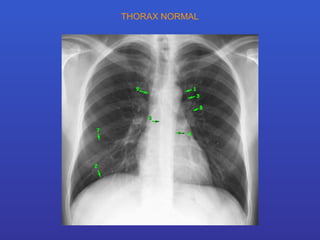

THORAX NORMAL